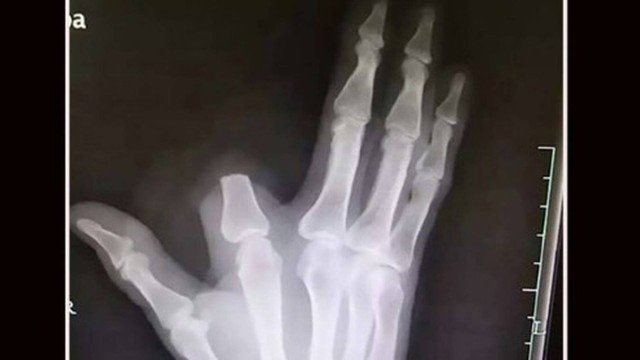

Rio – Um agricultor chinês, de 60 anos, tomou uma medida drástica após ser picado por uma cobra. Desesperado, Zhang decepou parte do dedo ferido a fim de evitar que o veneno se espalhasse. O caso aconteceu recentemente na zona rural de Shangyu (província de Zhejiang), de acordo com o “South China Morning Post”.

Mais do que isso: o paciente não apresentava nenhum dos sintomas daqueles picados por cobras venenosas de alto risco: problemas respiratórios, forte dor de cabeça e sangramento. Na verdade, o veneno da víbora que picara o agricultor é muito fraco, com efeito mínimo sobre humanos. Zhang cortou o pedaço do indicador à toa. E ele não pôde ser reimplantado.